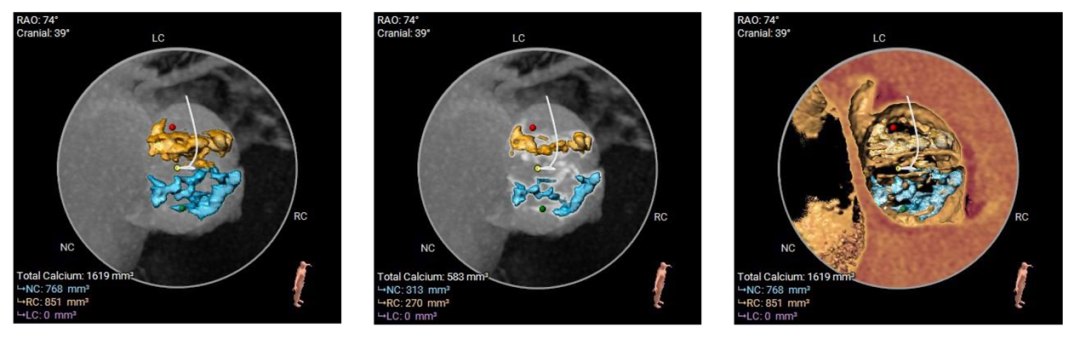

Type-0型二叶瓣,中-重度钙化伴瓣叶增厚,左冠开口高度偏低,右冠开口高度可,左冠瓣叶长度略大于冠脉开口上缘与瓣叶附着缘距离,左室流出道整体呈直筒型,瓦氏窦,窦管交界,升主动脉内径可,左室腔内径可,心室壁增厚,主动脉瓣环与水平面夹角51度,非横位心,主动脉弓距、弓角可 -双侧入路血管走形良好,整体入路条件可

使用沛嘉20mm球囊预扩,预装沛嘉TaurusElite AV23瓣膜,释放高度瓣上0-2mm